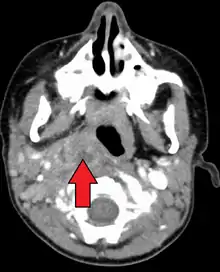

Retropharyngeal abscess

A computed tomography (CT) scan is the definitive diagnostic imaging test.[4]